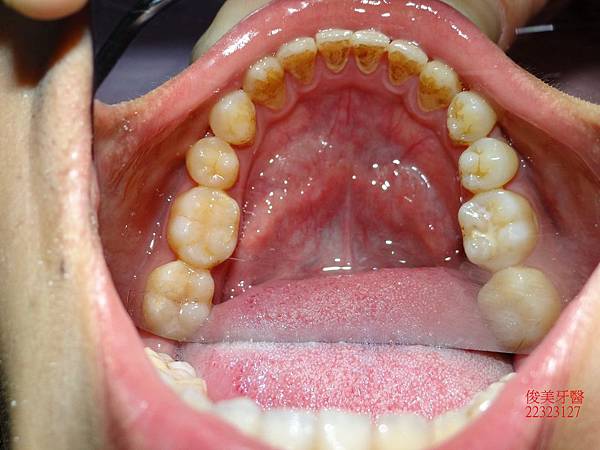

原始狀況~~

上顎牙弓形狀